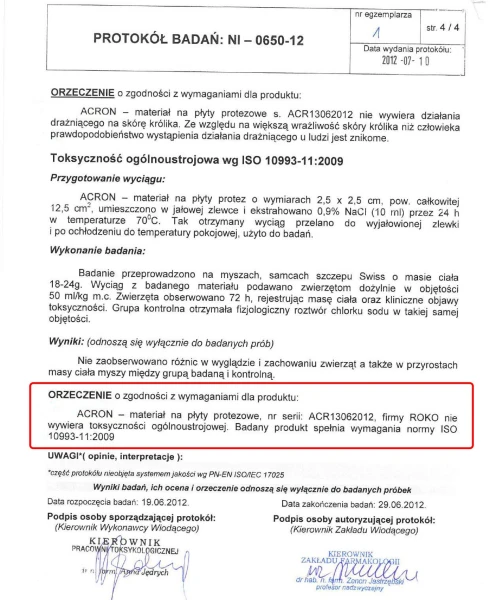

ACRON został gruntownie przebadany i przetestowany. Badania Narodowego Instytutu Leków wykazały, że nie zawiera substancji toksycznych i drażniących. Jest bezpieczny dla pacjentów i personelu medycznego.

DLA ALERGIKÓW

CERTYFIKACJA ISO